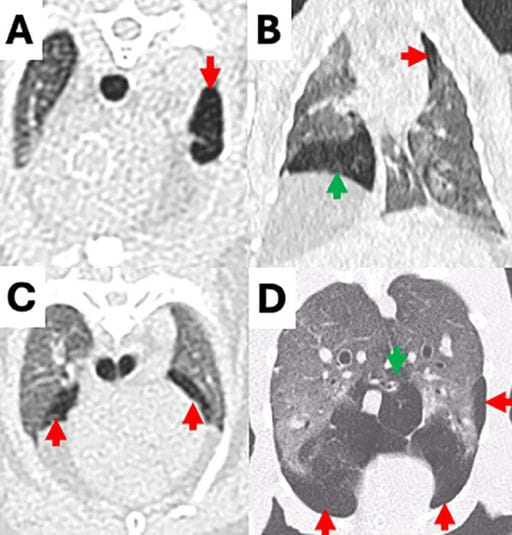

CT images of emphysematous hypoattenuating lung tissue in rabbits. (A) Unilobar in the left cranial lung lobe (red arrow), and multilobar in three different rabbits in (B) the left cranial (red arrow) and right middle (green arrow) lung lobes, (C) both cranial lung lobes (arrows) and (D) both caudal (red arrows) and accessory (green arrow) lung lobes.

PE was detected in 11.2% of rabbits (59/529). Affected rabbits had a mean age of 9 years, and the cranial lung lobes were most commonly involved. The median attenuation of emphysematous lung tissue (−905 HU) was significantly lower than nonemphysematous areas (−667 HU) and control lungs (−652 HU). Peripheral and bullous emphysema showed lower attenuation than diffuse types. No significant correlation was found between PE and lower respiratory tract clinical signs—44.1% of affected rabbits were asymptomatic. However, severe respiratory distress (e.g., open-mouth breathing, cyanosis) occurred in 10.2% of rabbits, all with advanced PE and poor prognosis. Secondary complications included rib fractures (5.1%) and pneumothorax (3.4%). In 15 rabbits with serial CTs, PE was progressive in 80% of cases.